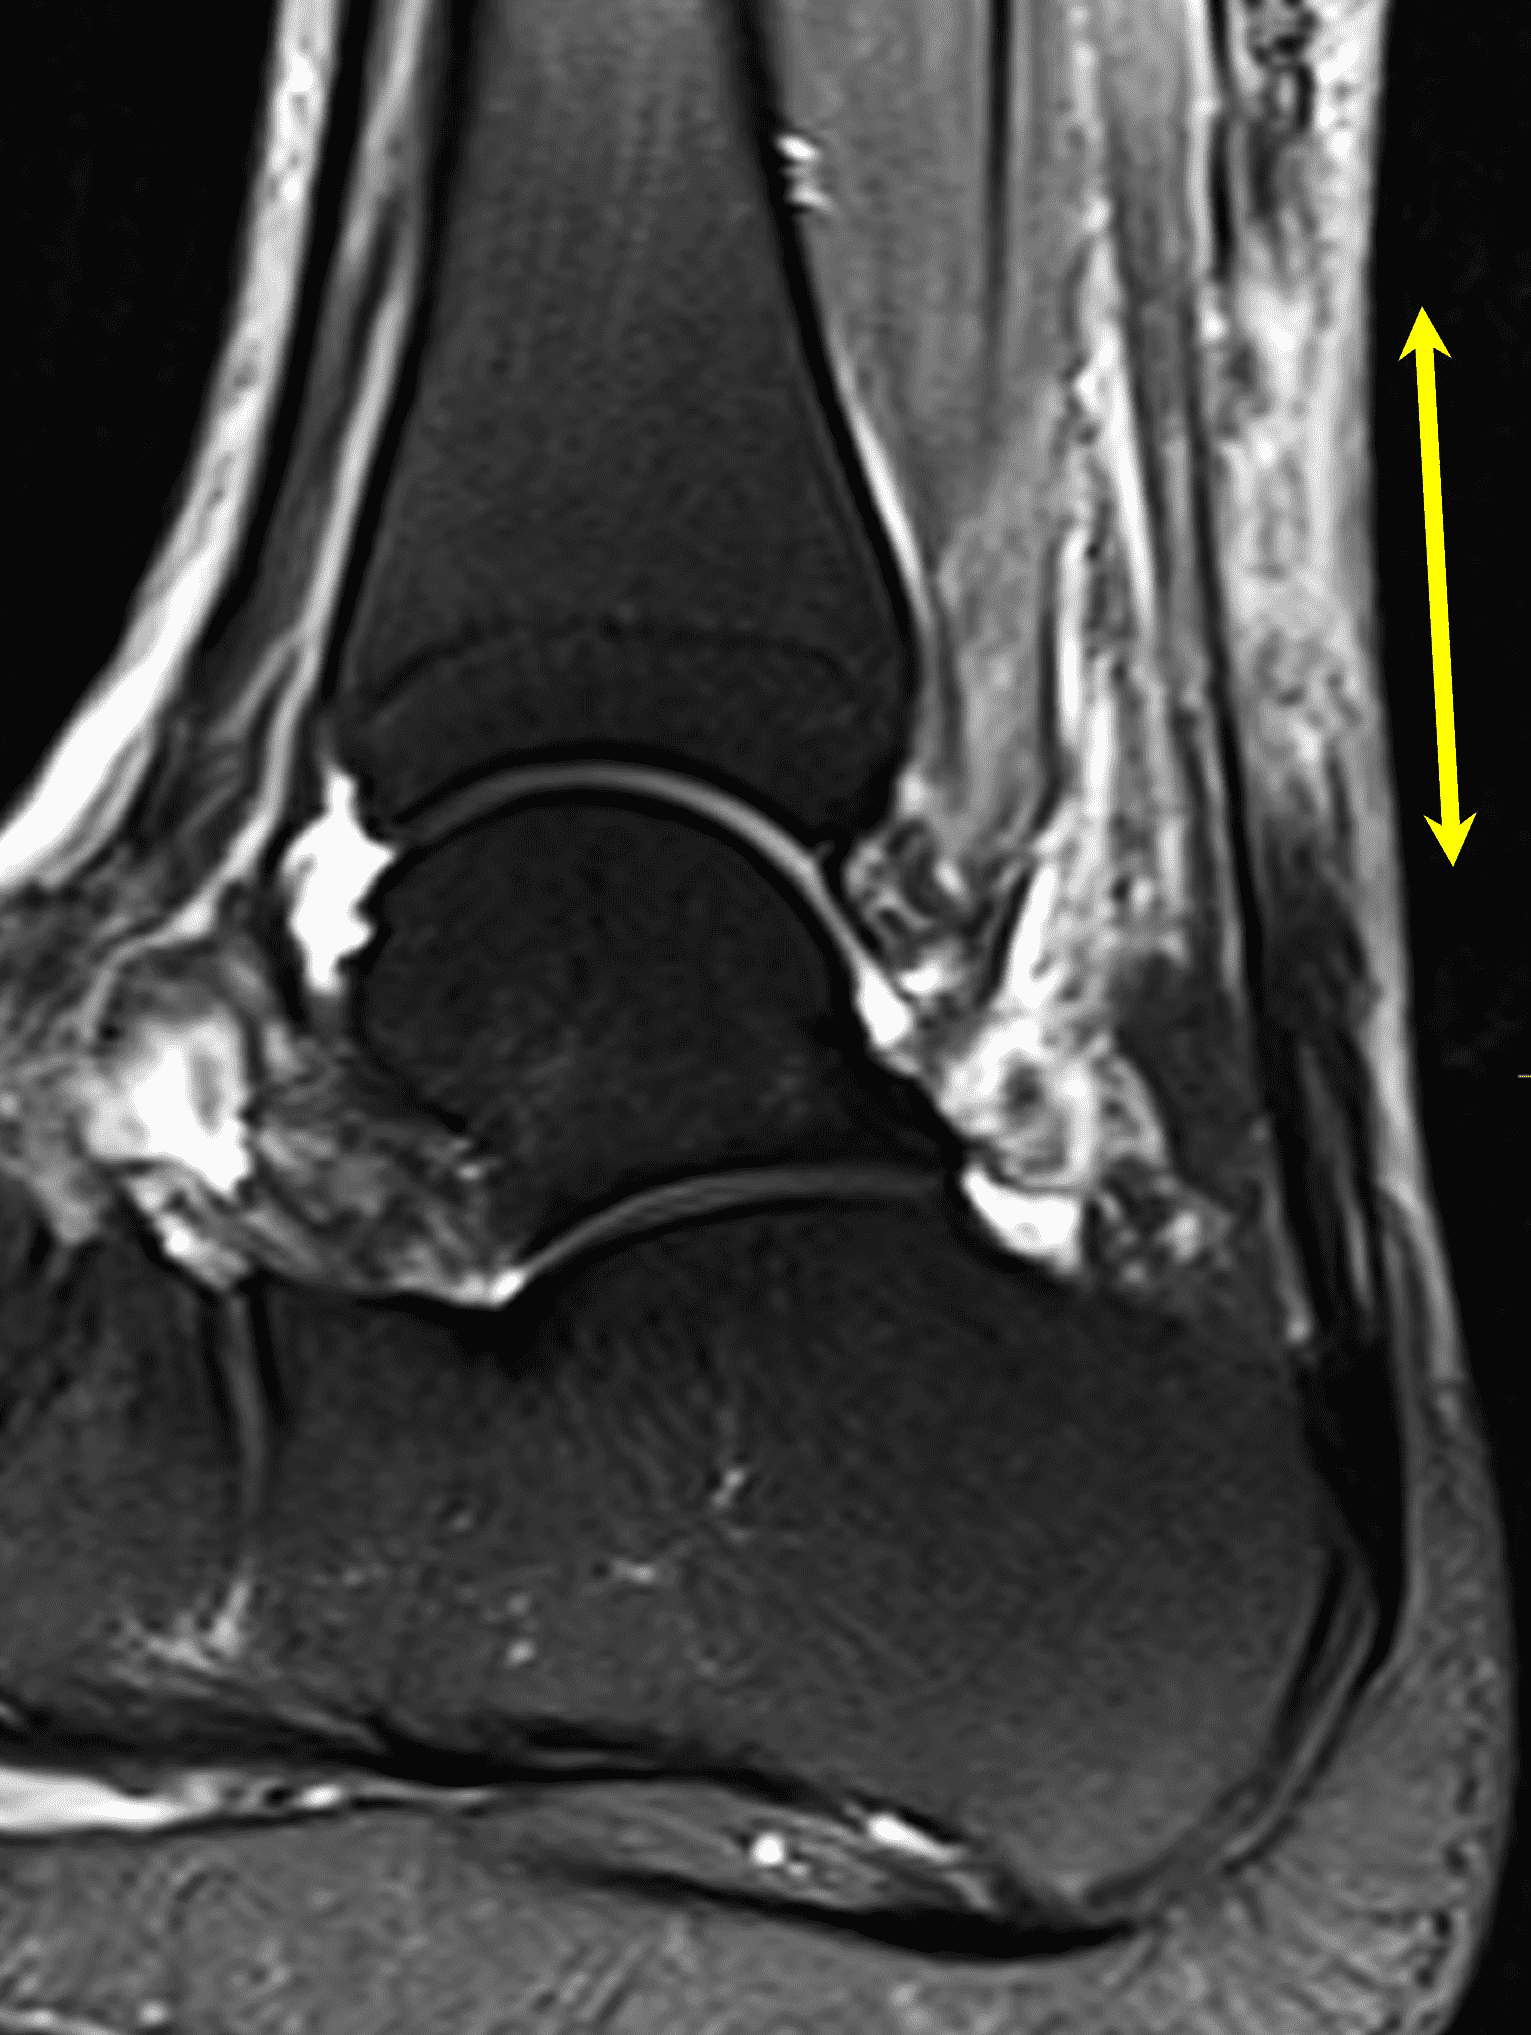

Figure 2: Complete Achilles tendon rupture. (2A) The lateral radiograph shows a thick and indistinct proximal Achilles tendon contour (arrows). (2B) A fat-suppressed T2-weighted image shows complete rupture of the tendon with a fluid-filled gap (yellow arrow) measuring 1.5 cm in length, located 10 cm cranial to the tendon insertion (blue arrow) and just distal to the edematous myotendinous junction (red arrow). The tear is superimposed on diffuse tendinosis. (2C) A sagittal T1-weighted image confirms the diffuse tendinosis. Fluid extends anteriorly into Kager’s fat pad (arrow) suggesting disruption of the anterior paratenon. (2D) A transverse fat-suppressed T2-weighted image through the proximal tendon shows no intact fibers (arrow), confirming the full-thickness rupture.